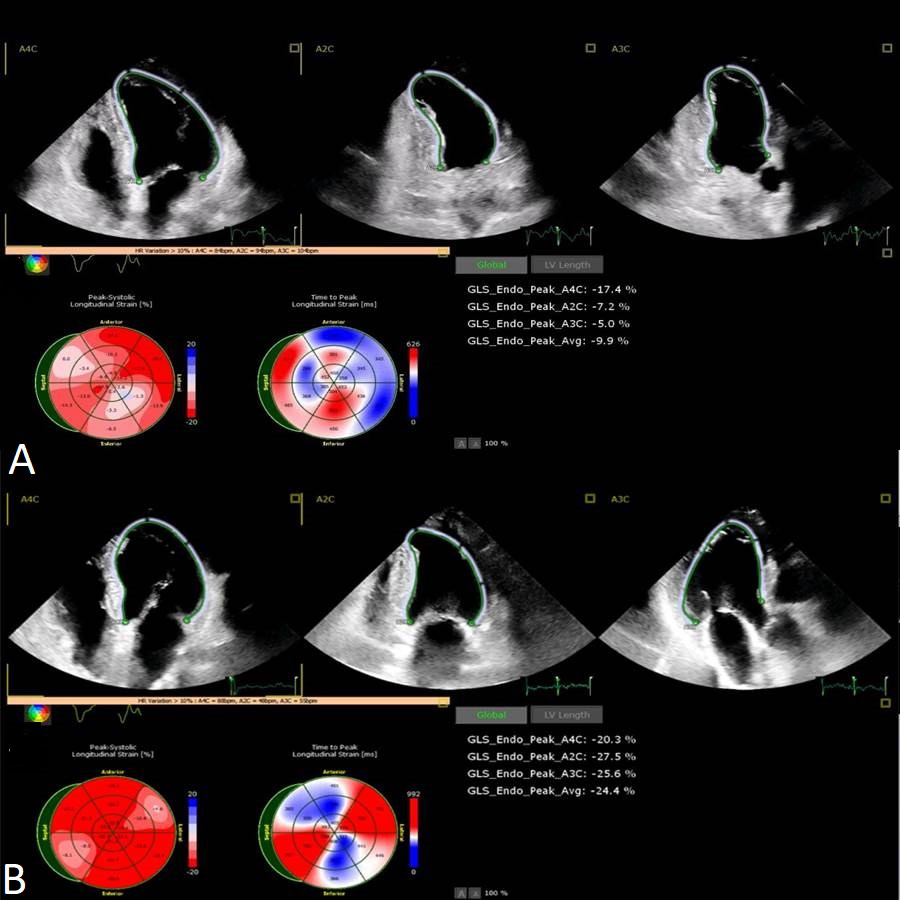

Strain TTE is a rigorous method of evaluating regional and global left and right myocardial function. It is angle independent and it requires a proper acoustic window. Strain images unfolded important information about patients with TS. By speckle tracking analysis, the systolic function of the left ventricle had a more delayed recovery compared to the calculated LV ejection fraction [28, 84, 85, 86]. Even though it is generally accepted that in the apical and midventricular variant the base of the LV is hyperkinetic, strain analysis revealed contractility impairment even in the “hyperkinetic” areas [36, 87]. LV strain assessment has prognostic value in the acute phase of TS patients [88]. In TS, the motion abnormalities are not subtle, especially in the apical variant. As a result, speckle tracking echography has a more pronounced role in the follow-up part rather than in the acute, diagnostic part. Kobayashi et al. [85] performed follow-up 3D strain echography at 4 weeks and 6 months after the diagnosis. They identified that regional abnormalities by peak systolic shortening and peak systolic thickening persisted at 4 weeks despite normalized LVEF (Fig. 4). The persistence of myocardial dysfunction assessed by LV strain was described at 4 weeks follow-up in Takotsubo patients [89].

Fig. 4.Speckle tracking echocardiography showing the improvement in global longitudinal strain and time to peak longitudinal strain from the acute phase (A) to 1 month follow-up (B). GLS, global longitudinal strain.